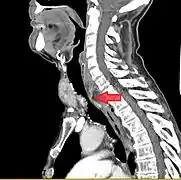

- Goitre comprimant la trachée cervicale.

Rétrécissement trachéal (flèche rouge). Tomodensitométrie (coupe transversale).

Même tumeur (coupe sagittale).